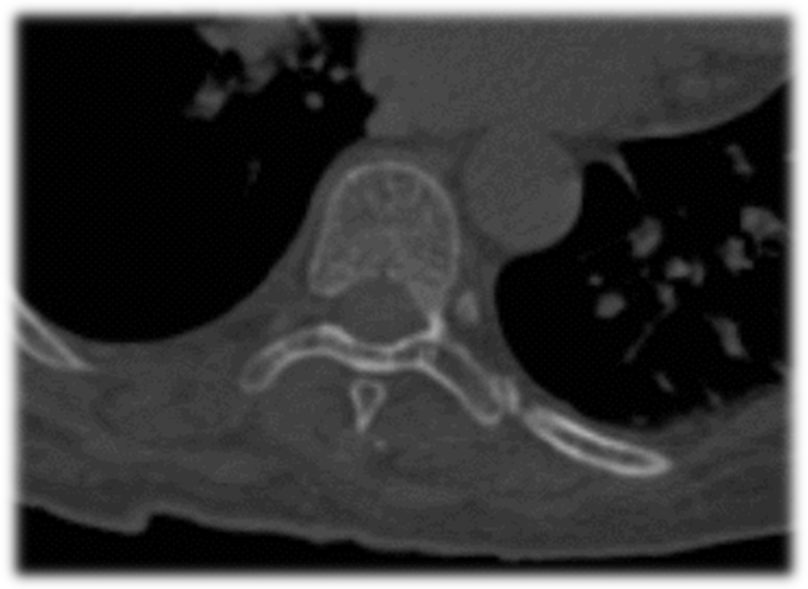

术前CT

术前MRI

术前诊断:1.胸腰椎后凸畸形,2.重度骨质疏松症,3.Kummell病II期,4.胸椎椎管狭窄,5.黄韧带骨化症,6.高血压病。